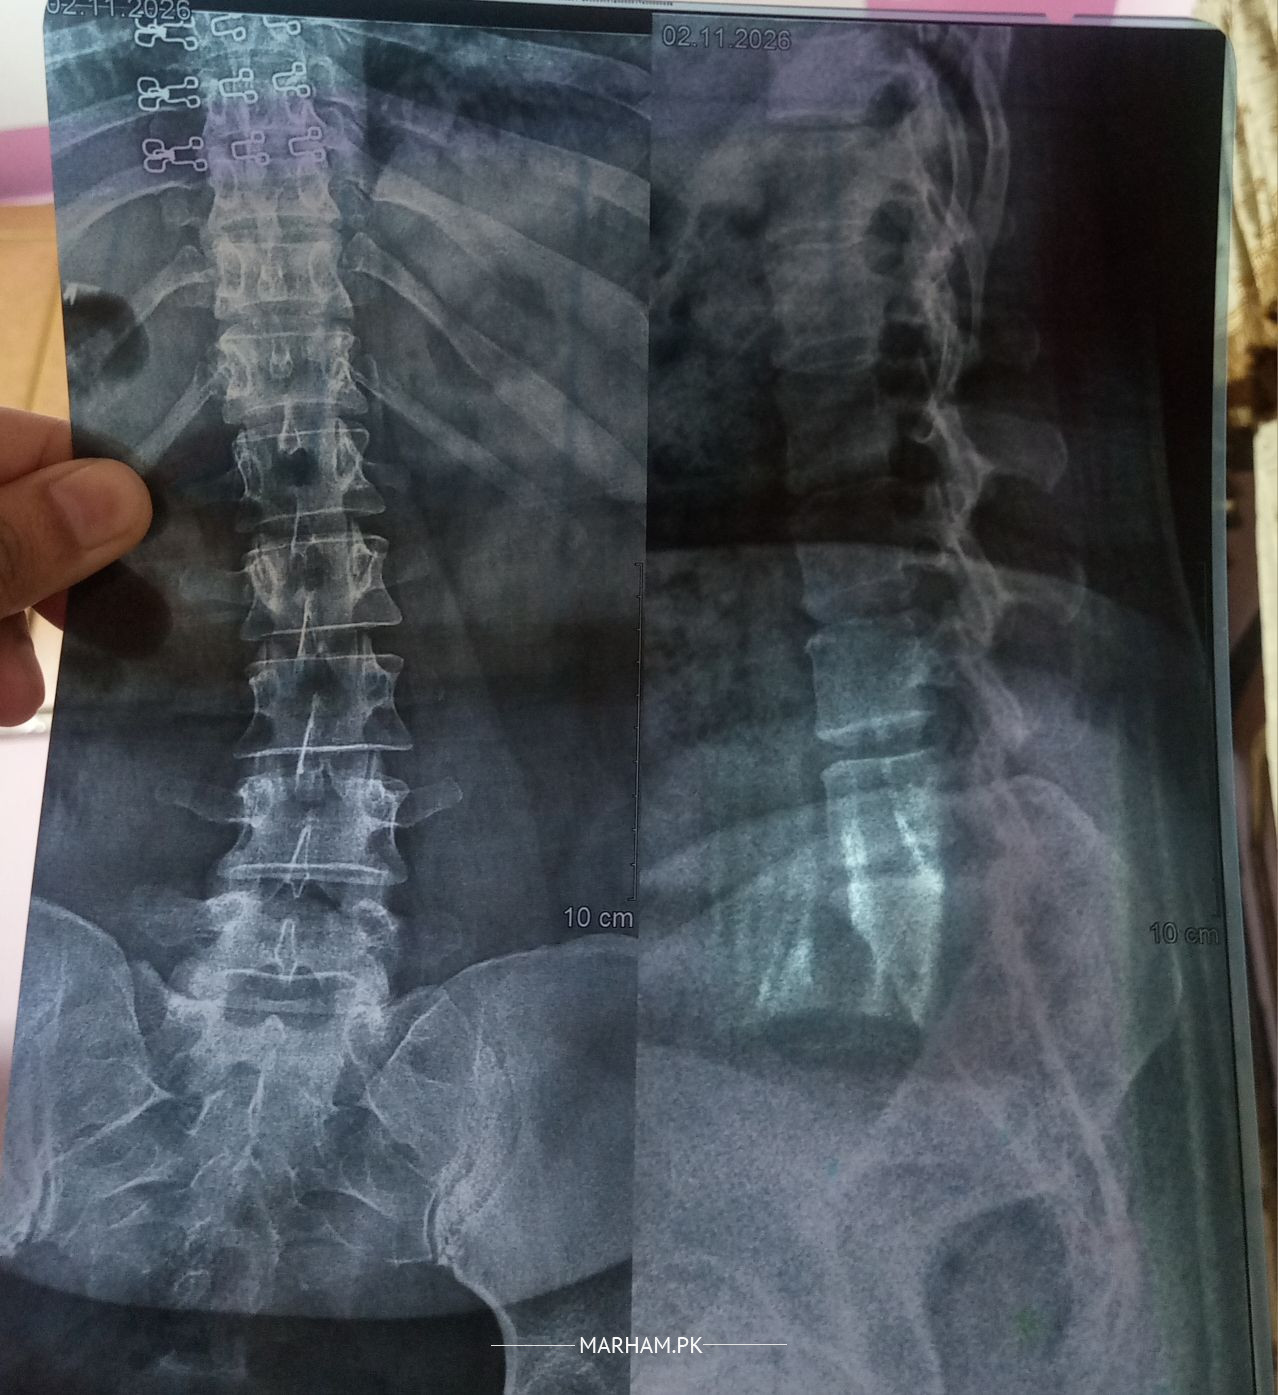

XRay spine looks that you have significant muscle spasm. Better to see any orthopedic or Spinal Surgeon near you for proper assessment and than management.

Any problem in the spine can cause muscle spasm, need to establish problem in the spine which is the source of this muscle spasm

May need MRI Lumbosacral Spine, it will help in establishing the diagnosis